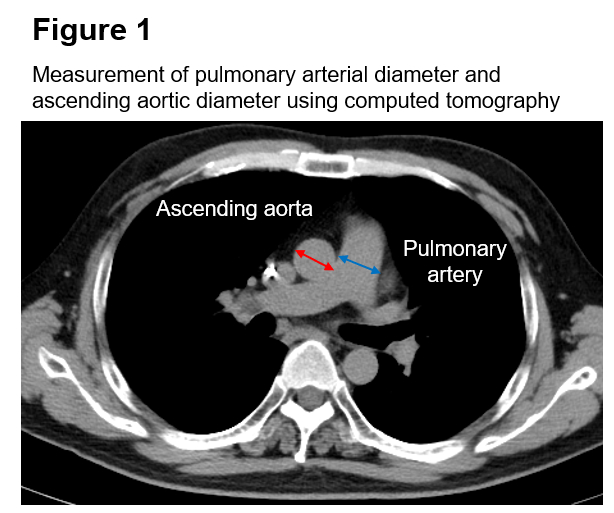

Methods: We retrospectively examined 73 consecutive patients who underwent M-TEER for severe mitral regurgitation between April 2020 and March 2025. Chest CT performed within 3 months before the procedure was used to measure the diameters of the main PA and Ao. Transverse axial main pulmonary arterial diameter and minimum ascending aortic diameter were both measured at the level of PA bifurcation (Figure 1). The PA/Ao was calculated as the former divided by the latter. Patients were divided into two groups: higher PA/Ao (≥1.0) and lower PA/Ao (<1.0). The primary outcome was a composite of all-cause death and hospitalization for worsening HF.